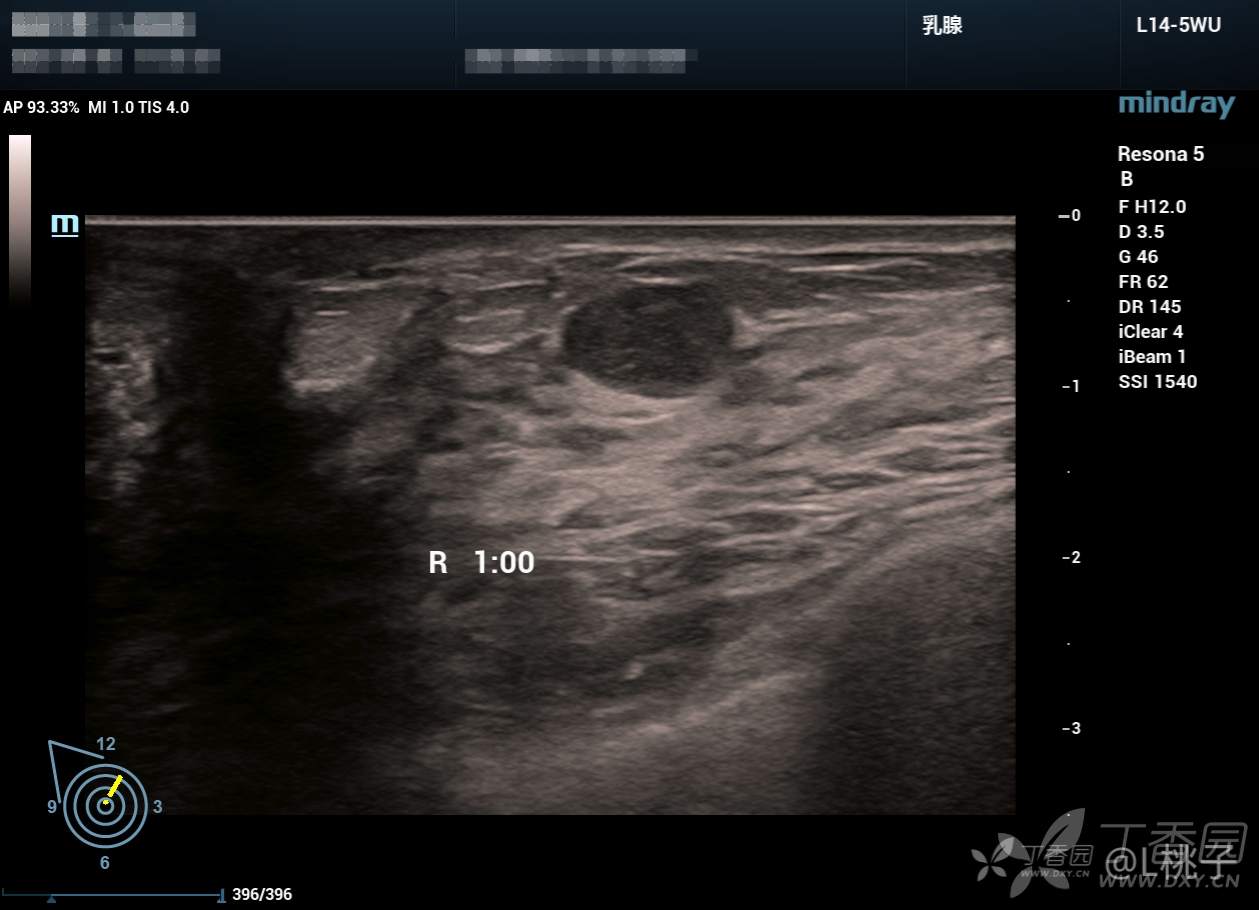

发部分乳腺结节的病例

大家考虑一下分级

病例1: